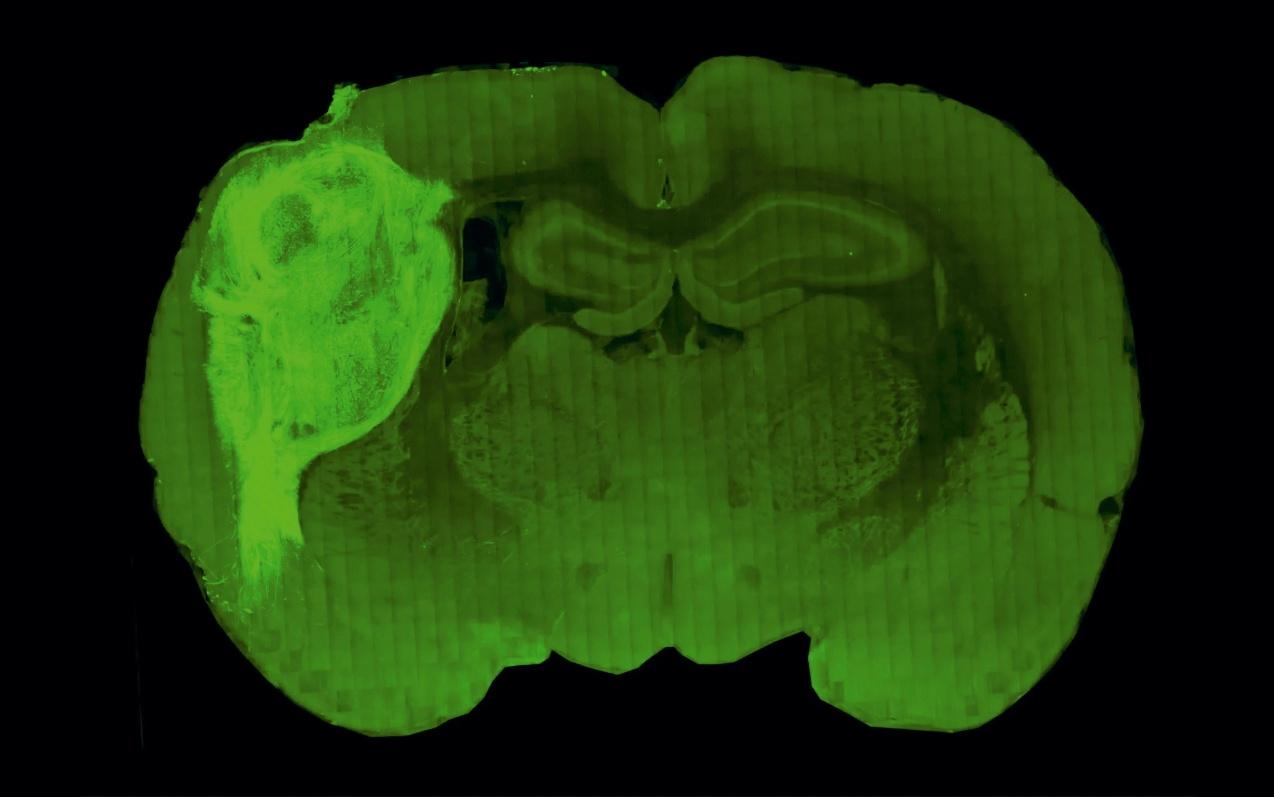

Des neurones d’homme dans la tête d’un rat

£ Une nouvelle façon d’étudier les neurones humains consiste à les transplanter dans un cerveau de rat.

£ Les amas de neurones transplantés – appelés « organoïdes » –se développent correctement, créent des connexions neuronales avec le tissu de l’animal et s’intègrent à ses réseaux cérébraux.

£ Les chercheurs pourront alors tenter de comprendre pourquoi des neurones humains « maturent » mal dans certaines pathologies cérébrales.

Or aujourd’hui, dans la revue Nature, des neuroscientifques de l’université de Stanford, aux États-Unis, annoncent qu’ils ont trouvé un nouveau moyen d’étudier des neurones humains afn de les regarder grandir et vieillir. Comment ? En transplantant des « organoïdes » – des amas de cellules

semblables à du tissu – de cerveau humain dans le cerveau de rats âgés de quelques jours seulement, quand ce dernier n’est pas encore complètement formé. Sergiu Paşca et ses collègues ont ainsi montré que des neurones humains et d’autres cellules cérébrales se développent et s’intègrent correctement chez leurs hôtes animaux, intervenant même dans certains circuits cérébraux fonctionnels des animaux qui analysent des sensations ou contrôlent des comportements.

La région brillante à gauche de ce cliché montre une ébauche de cerveau humain, d’abord produit dans une boîte de culture, puis inséré dans le cerveau d’un rat. Le minicerveau humain fonctionne et communique avec celui du rat qui l’environne.

17 % DU CERVEAU DE CE RAT EST… HUMAIN « Nous avons découvert que, si nous transplantons l’organoïde juste à la naissance du raton, il devient jusqu’à neuf fois plus grand en quatre ou cinq mois », a déclaré Sergiu Paşca. De sorte que le tissu cérébral humain représente environ un tiers de l’un des hémisphères cérébraux du rat devenu adulte (voir la fgure page 17).

Sur cette coupe transversale du cortex de l’un des rats de Sergiu Paşca (à gauche), les pointillés délimitent la frontière entre le cerveau humain et celui du rat. La coloration révèle que les vaisseaux sanguins de l’animal ont richement vascularisé le gre on humain. Dans une autre expérience (à droite), la lumière verte dans les neurones du rat, situés loin de l’organoïde implanté, montre que ces derniers ont créé des synapses fonctionnelles avec les neurones humains.